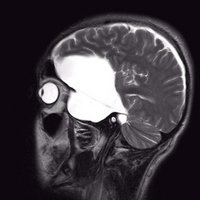

Arachnoidalzyste

Arachnoidalzyste T2 sagittal